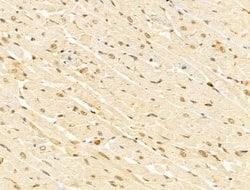

Invitrogen™ GABPB1 Polyclonal Antibody

Antibody detects endogenous levels of total GABPB1.

| Immunohistochemistry (Paraffin), Western Blot, Immunocytochemistry | |

| A synthesized peptide derived from human GABPB1(Accession Q06547), corresponding to amino acid residues V264-D314. | |

| Human, Mouse, Rat | |